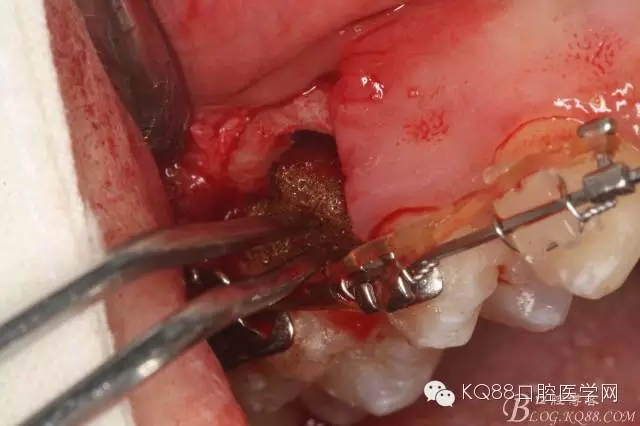

圖14.用小球鉆縱分15牙根

圖15 .微創(chuàng)挺把15牙根縱分成近遠(yuǎn)中兩塊

圖16.微創(chuàng)挺挺松近中根面部分,從16與14之間間隙出來

圖17.血管鉗取出近中部分15牙根